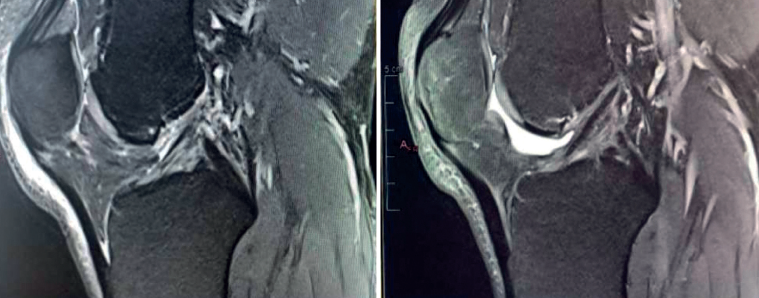

We now know from the histological study of ACL remnants after rupture that the ligament has some intrinsic capacity for spontaneous healing, as evidenced by the presence of vascular buds, nerve endings and cells with healing capacity in the remnant tissue(3). Further evidence of this self-repairing capacity can be found in the good functional results published in some patients treated on a conservative basis, especially older individuals with lesser physical demands(4)(Figure 1).

Despite this, it is true that complete healing of the ACL without surgical treatment after rupture is rare. Among other reasons, this is because of the presence of synovial fluid inside the joint, which hinders the formation of a contained hematoma between the two extremities of the torn ligament (a necessary preliminary step for tissue healing). To overcome this adverse joint environment and improve the results of ACL reconstruction, a number of authors(5) have for some years recommended preserving the remains of the torn ligament, taking advantage of its biological capacity to facilitate its integration into the bone tunnels and improve proprioception.